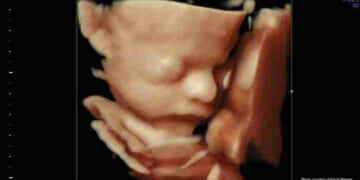

“You really think that this is an image of a human being?” Abortion advocates will often ask this question while showing an image of a dog embryo. (click here to see an example image) If you say yes, the abortion advocate will ruthlessly mock…